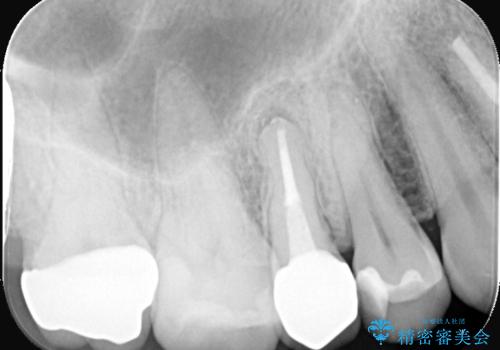

- 何年も前に入れた詰め物が取れたとのことで来院されました。残っている歯の量と強度のことをお話しし、被せものでの治療となりました。

もともとの修復材料とう蝕を除去し、CR裏層の上、オールセラミッククラウンにて修復しました。